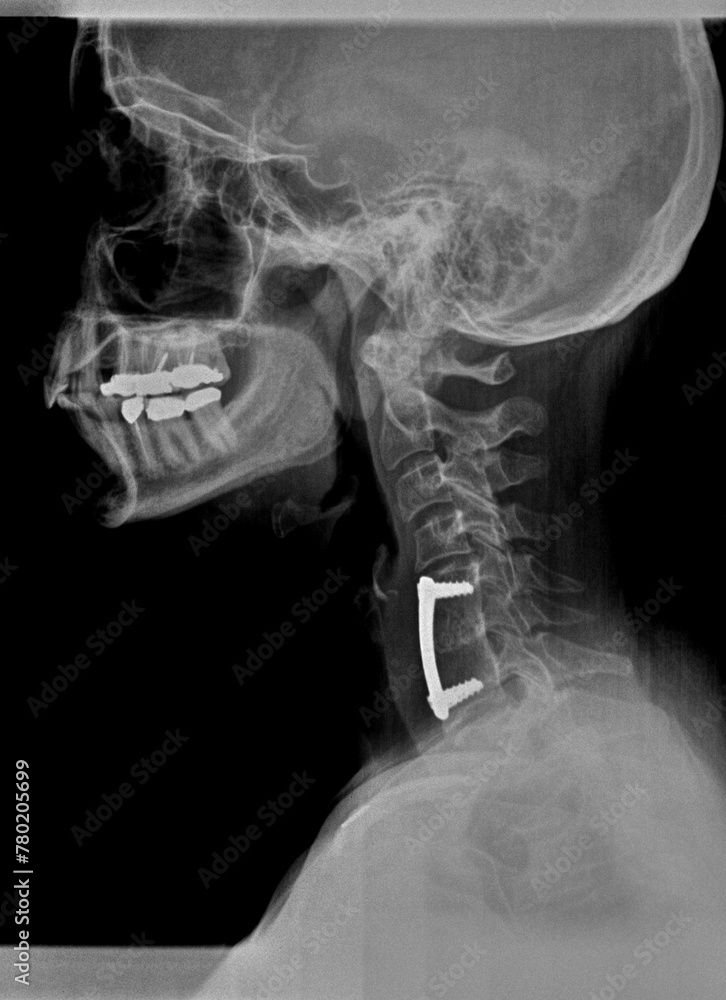

ACCF is a procedure involves removing one or more vertebral bodies (the large, block-like parts of the vertebrae) and the adjoining discs. This is done to decompress the spinal cord and nerves. After removing the damaged bone and discs, a void is left. To restore stability, the surgeon fills this space with a structural bone graft. This can be a fibular strut graft (bone from a cadaver) or a synthetic cage packed with bone material. A metal plate and screws are then typically fixed to the vertebrae above and below the gap. Over time, the vertebrae fuse together with the graft, creating a single, solid segment of bone intended to stabilize the spine.